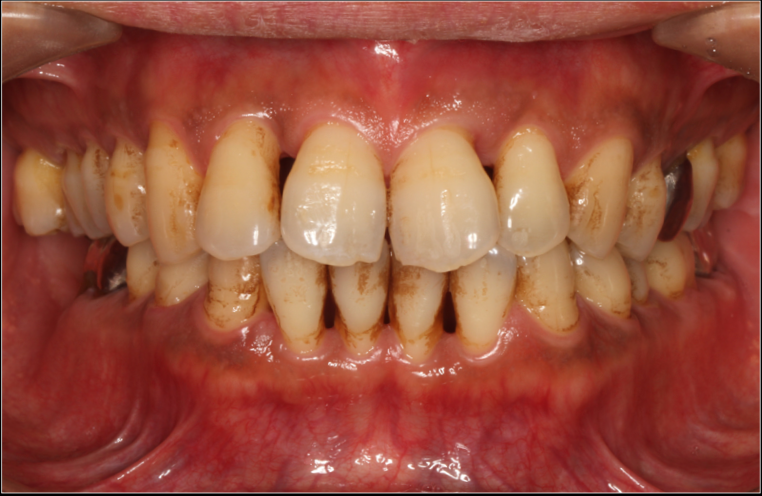

重度歯周病の症例

重度の歯周病では、審美的な問題もあるため、歯科医院に行きにくいという方も多いです。しかし、このまま放置してしまうと、多くの歯を失うことになり、身体的にも経済的にも負担が掛かる可能性があります。

重度歯周病は、歯周病が進行する最終段階と言えます。

骨の約分が吸収(溶かされている)状態であることから、